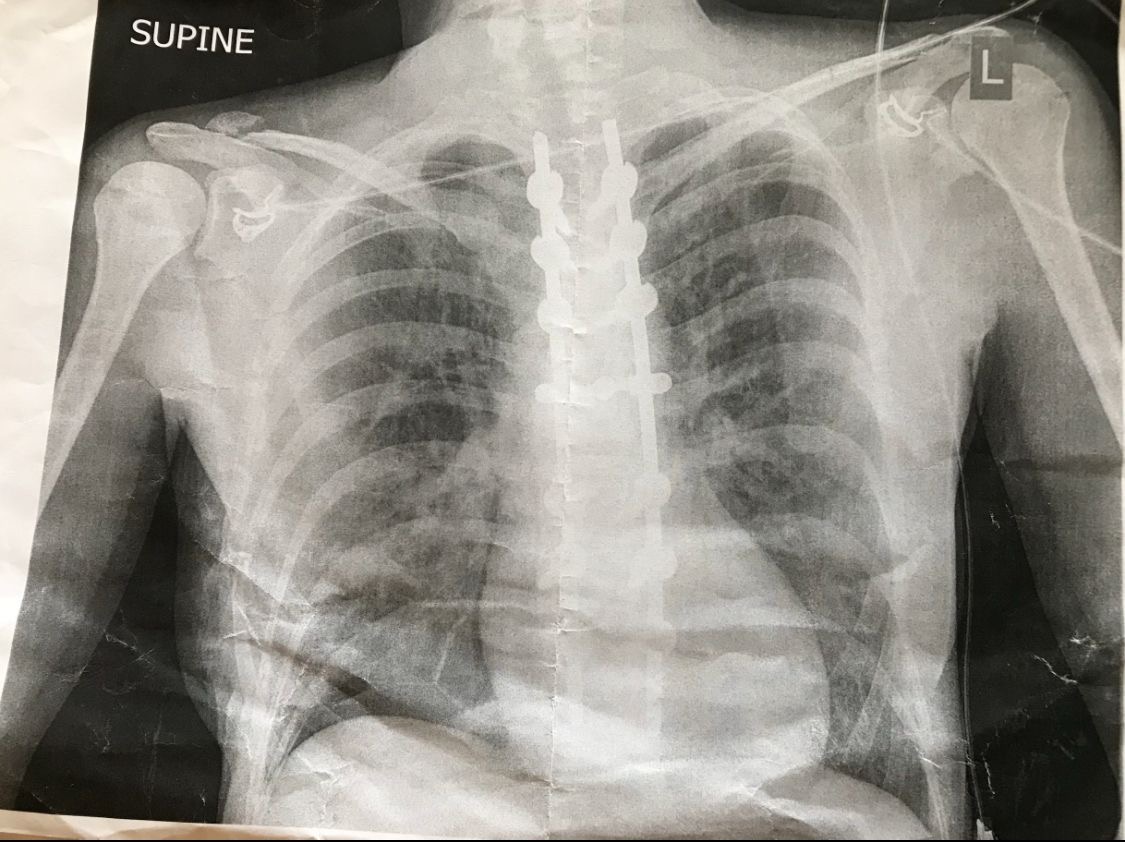

Spinal implants following an SCI promote host tissue regeneration and nerve plasticity and reconnection. These can help to recover some muscle function. Following her accident, my mum had surgically implanted titanium rods to stabilise her vertebrae, allowing the facet joints to heal. Her X-Ray is shown below.

I mentioned earlier that I struggled to categorise some of my mum’s devices, and this one is no exception. I have concluded that her rods are orthotic, since they modify rather than replace the damaged vertebrae (I encourage discussion in the comments if you disagree!).